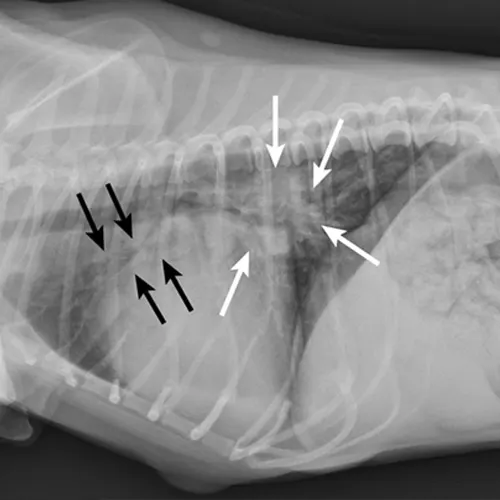

Primary cardiac disease that leads to CHF-related pulmonary edema commonly causes diffuse (perihilar in the dog) or variable (in the cat) interstitial and alveolar patterns. The vertebral heart score (VHS) is an objective method for evaluating the size of the cardiac silhouette (see Steps to Measure VHS). Certain cutoff values are used to determine whether acute respiratory distress is primarily pulmonary or cardiac in origin and to guide initial therapy for stabilization and planning for definitive cardiac or respiratory workup. A VHS <11.4 in the dog can help rule out mitral valve disease–related CHF as a cause for respiratory signs.3 Although an increased VHS can be associated with primary cardiac disease, it is not a specific characteristic in small-breed dogs because of their thoracic conformation.3 In the cat, a left lateral VHS ≤7.9 can reasonably rule out the presence of heart disease.4 Additional radiographic changes associated with primary cardiac disease include left atrial enlargement and pulmonary venous distension (Figures 1 and 2). Pleural effusion can be associated with CHF and primary pulmonary disease. A miliary pattern and/or solitary soft tissue densities in the lungs are indicative of primary pulmonary disease (Figure 3). Hyperinflation of the lung and distinct peribronchial markings are supportive of lower airway disease, although peribronchial markings can be found in the cat with CHF.

Right lateral thoracic radiograph of a dog that was presented with labored breathing and a moist cough. The patient had a history of a heart murmur, and the breathing pattern was synchronous with increased effort on inhalation. Thoracic auscultation revealed diffuse, soft moist crackles and a 4/6 left systolic heart murmur over the mitral region. Butorphanol and furosemide were administered and the patient was allowed to rest with supplemental oxygen before radiography. Radiographs showed a VHS of 12.5, significant left atrial enlargement (white arrows), and pulmonary venous distension (black arrows) consistent with left-sided heart failure. Mitral valve insufficiency caused by valvular endocardiosis was confirmed with echocardiography.